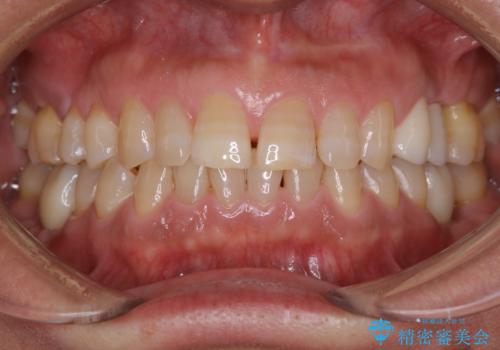

30代女性 前歯の長さを変える オールセラミック

施術前は、ベニヤという修復物が歯ぐきの深い位置まで、貼り付けられている状態でした。

極東アジア人には珍しい豊富な角化歯肉があったため、極力審美的な方法での手術で歯の長さを改善し、セラミックを製作しました。

被せものの種類:ジルコニアオールセラミック スタンダード

(4番目の歯:e.max プレスクラウン)